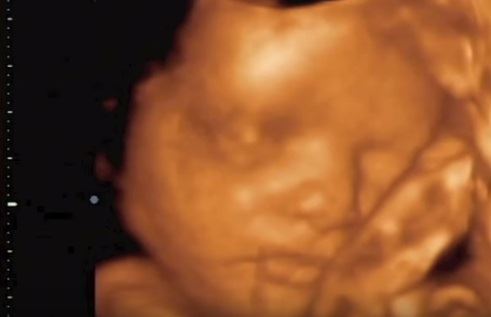

Foto: Youtube Printscreen / I-baby

Na snimku se jasno vidi beba koja se neprestano pomera, pravi grimase, ručka, plače, tako slatko se mazi o unutrašnju stranu maminog stomaka i trlja okice!